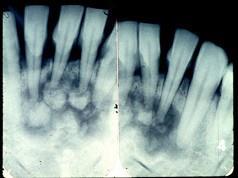

问题 图为牙骨质瘤的X 线表现,关于此病描述不正确的是 ( )

选项 A.牙髓活力测试是阴性的 B.来源于牙胚的牙囊或牙周膜 C.X 线显示根尖周围有不透光的阴影 D.生长缓慢,一般无自觉症状 E.肿瘤紧贴牙根部,可单发或多发

答案 A